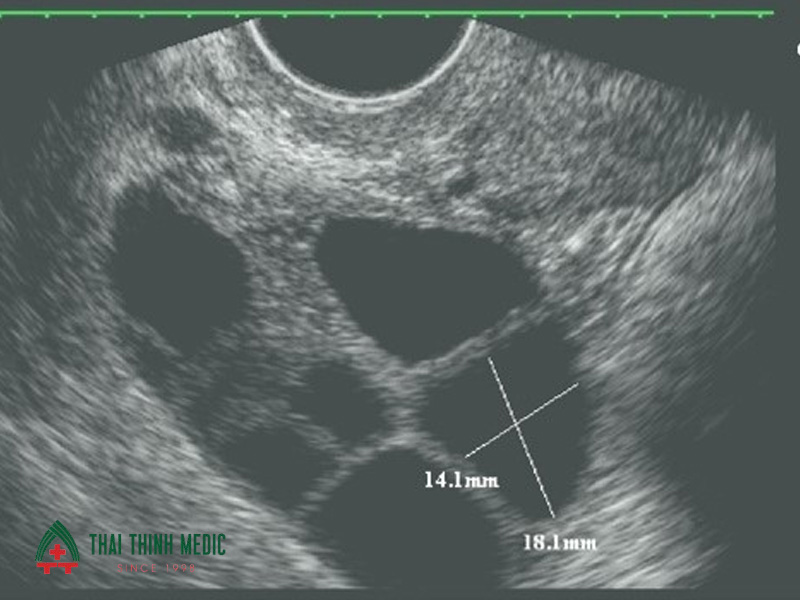

- Lần 3: Từ ngày 12 – 14, đây là thời điểm vàng để quan sát nang trứng đạt kích thước 18–22mm – dấu hiệu cho thấy trứng sắp rụng. Khi đó, bác sĩ sẽ tư vấn thời điểm quan hệ tối ưu hoặc lên kế hoạch bơm tinh trùng (IUI), kích rụng trứng tùy trường hợp.

- Độ chính xác cao, hình ảnh cận cảnh giúp bác sĩ đo được kích thước nang trứng với sai số chỉ vài milimet.

Siêu âm canh trứng đo chính xác kích thước nang trứng